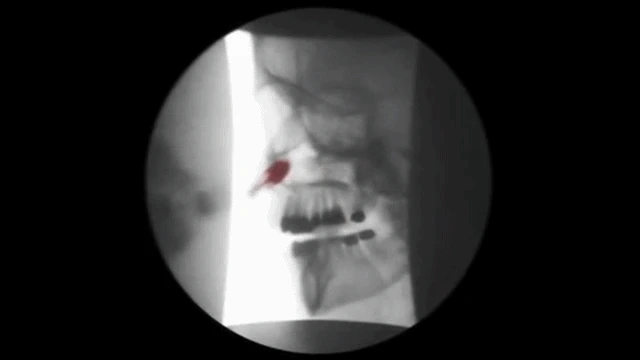

4. 두개안면교정술

CFRT 라는 두개안면 교정술을 시행하는데

비강과 인두 사이에 위치한 두개안면 구조물에

조그만 치료용 풍선을 넣어 공간을 확장시키고

원래의 위치로 복구 시켜주는 비대칭 교정의

가장 중요한 비수술적 요법 입니다.